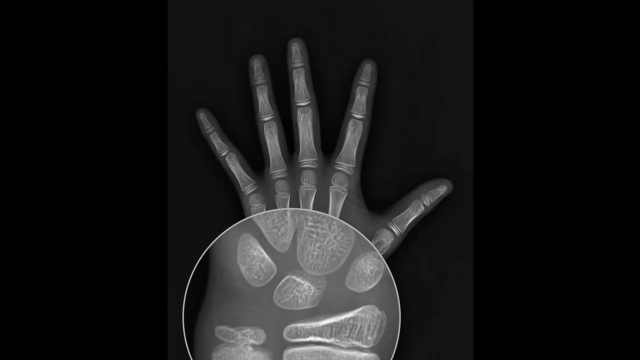

成像清晰度是骨齡評(píng)估準(zhǔn)確性的基石。安智齡X射線骨齡儀采用的85μm像素尺寸平板探測(cè)器,屬于行業(yè)高標(biāo)準(zhǔn)配置。像素高達(dá)920萬,高像素確保了骨骼影像的細(xì)膩呈現(xiàn),特別是骨骺線邊緣、骨化中心密度等關(guān)鍵細(xì)節(jié)清晰可辨。這為醫(yī)生提供了可靠的影像依據(jù),從源頭上減少了因圖像模糊導(dǎo)致的誤判可能。高清成像直接提升了診斷信心。當(dāng)骨齡影像片中骨骼細(xì)節(jié)一目了然時(shí),醫(yī)生無需費(fèi)力解讀模糊區(qū)域,可以更快速、更肯定地做出判斷。這種技術(shù)保障,尤其有助于在評(píng)估生長(zhǎng)發(fā)育邊界性案例或進(jìn)行精細(xì)分期時(shí),提供更明確的影像證據(jù)。

在兒科內(nèi)分泌的臨床實(shí)踐中,X射線骨齡儀是評(píng)估兒童生長(zhǎng)發(fā)育情況的重要工具,其技術(shù)特性為診療提供了可靠支持。設(shè)備采用低劑量數(shù)字成像技術(shù),單次檢測(cè)的輻射劑量符合國(guó)際**標(biāo)準(zhǔn),且通過智能參數(shù)調(diào)節(jié)功能,在保證圖像清晰度的同時(shí)減少不必要的輻射暴露。其關(guān)鍵優(yōu)勢(shì)體現(xiàn)在評(píng)估精度與數(shù)據(jù)連貫性上。設(shè)備配備高分辨率探測(cè)器,可清晰捕捉腕骨、掌骨及指骨的細(xì)微結(jié)構(gòu)變化,結(jié)合標(biāo)準(zhǔn)化骨齡評(píng)估系統(tǒng),能減少人為讀片誤差,提升結(jié)果一致性。對(duì)于需要長(zhǎng)期監(jiān)測(cè)的病例,系統(tǒng)可存儲(chǔ)歷次檢測(cè)數(shù)據(jù)并生成動(dòng)態(tài)生長(zhǎng)曲線,幫助醫(yī)生觀察骨齡進(jìn)展與實(shí)際年齡的偏離趨勢(shì),為判斷生長(zhǎng)潛能或制定干預(yù)方案提供客觀依據(jù)。此外,設(shè)備操作流程標(biāo)準(zhǔn)化程度較高,從兒童手部拍攝固定到影像采集出報(bào)告只需1分鐘,且支持?jǐn)?shù)字化報(bào)告輸出,便于醫(yī)生與家屬溝通檢測(cè)結(jié)果。整體而言,X射線骨齡儀通過技術(shù)優(yōu)化與功能整合,為兒童生長(zhǎng)發(fā)育評(píng)估提供了量化、可追溯的醫(yī)學(xué)證據(jù)。安智齡X射線骨齡儀,采用高清影像技術(shù),確保檢測(cè)結(jié)果清晰準(zhǔn)確,值得信賴!